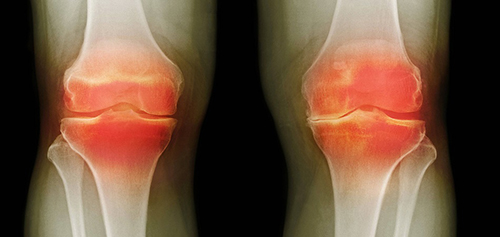

โรคข้อที่พยายามจะ "วินิจฉัย" แยกกันในประเทศไทยนั้น ในประเทศญี่ปุ่นได้รวมเข้าเป็นหนึ่งเดียวมานานแล้ว นั่นก็คือ "การสะสมเกลือในข้อ" ซึ่งอาการดังกล่าวได้แก่:

- เกาต์

- ข้ออักเสบ

- ข้อเสื่อม

- กระดูกสันหลังเสื่อม

- รูมาตอยด์

- กระดูกพรุน

- ถุงน้ำข้ออักเสบ

- เยื่อหุ้มข้ออักเสบ

- ถุงน้ำไขข้อ (ก้อนซีสต์)

นี่เป็นเพียงรายชื่อโรคอย่างย่อเท่านั้น โรคอื่น ๆ ล้วนเป็นเพียงกลุ่มย่อยของพยาธิสภาพหลักทั้ง 9 ประเภท เช่น โรคข้อสะโพกเสื่อม (Coxarthrosis) ก็เป็นชนิดหนึ่งของโรคข้อเสื่อม (Osteoarthritis) เป็นต้น